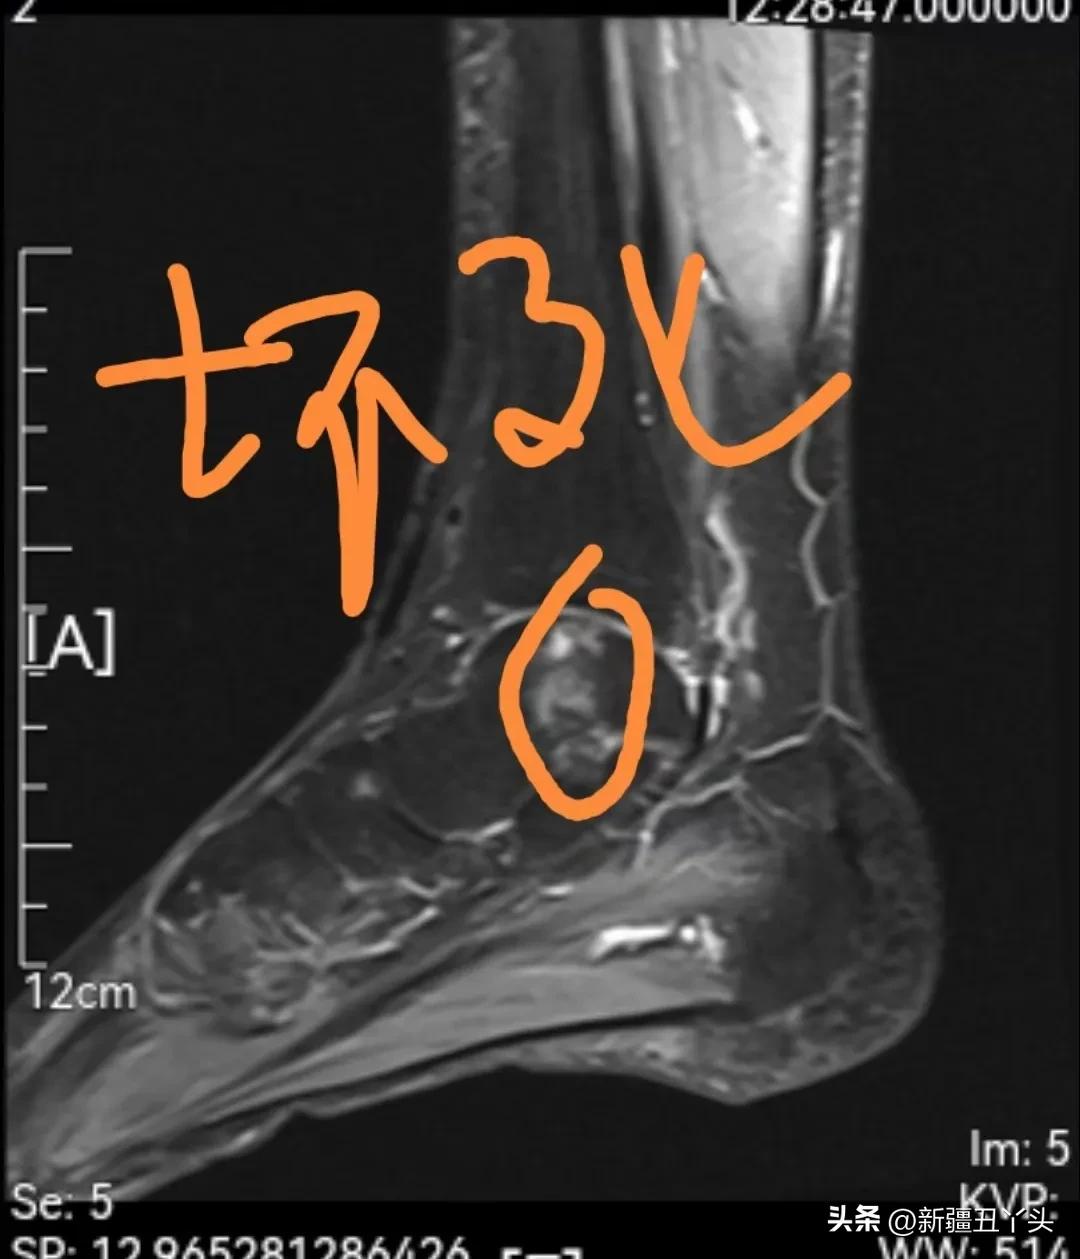

2020年10月18日,我一跤摔成了左踝关节距骨坏死。由于左踝长期肿痛,根本无法多走多动。